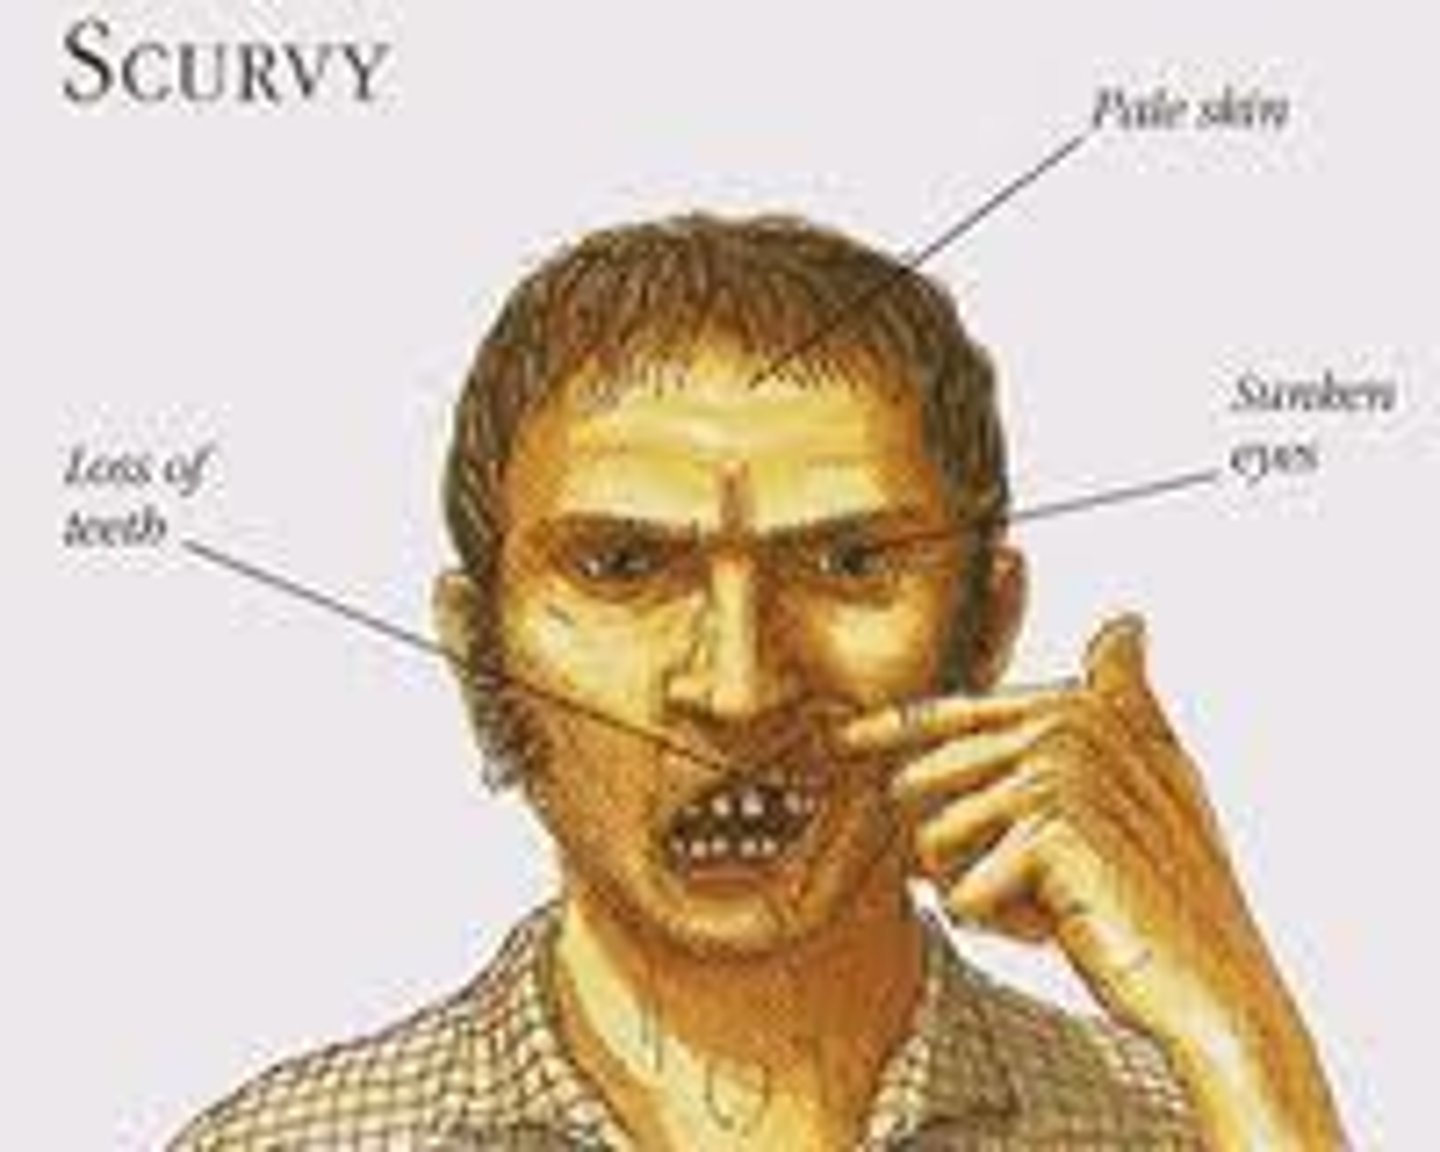

Swollen gums, mucosal bleeding, poor wound healing, petechiae, corkscrew hair

Scurvy (vitamin C deficiency: can't hydroxylate proline/lysine for collagen synthesis)

Ascorbic Acid